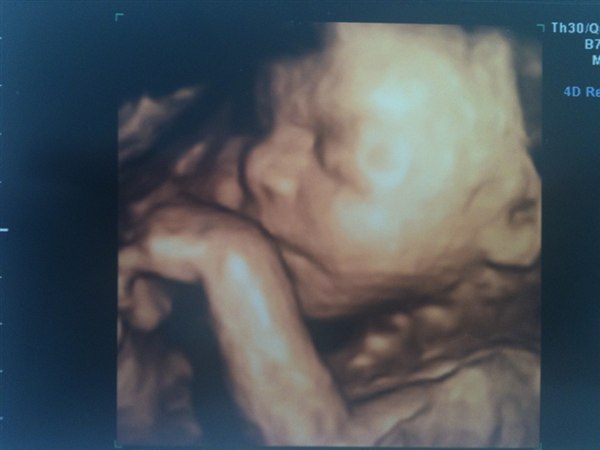

så jeg gjorde det, og jeg har slet ikke fortrudt det, det var en fantastisk oplevelse og det var godt jeg gjorde det, fordi det viste sig at det var en dreng jeg ventede og ikke en pige!